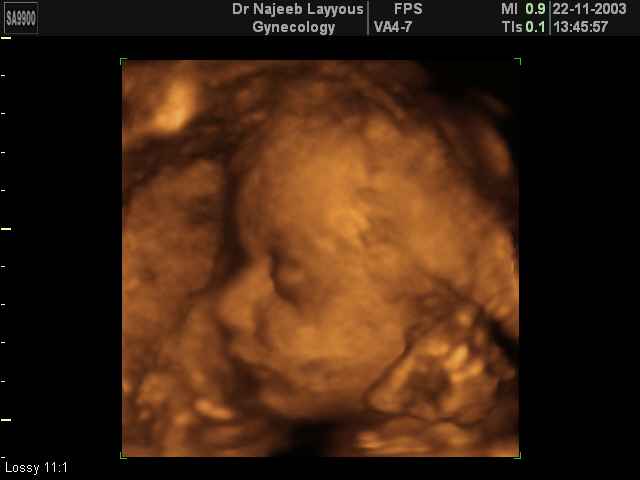

- 3D Fetal Profile Ultrasound Scan Photos

3D Fetal Profile Ultrasound Scan Photos | Dr N Layyous